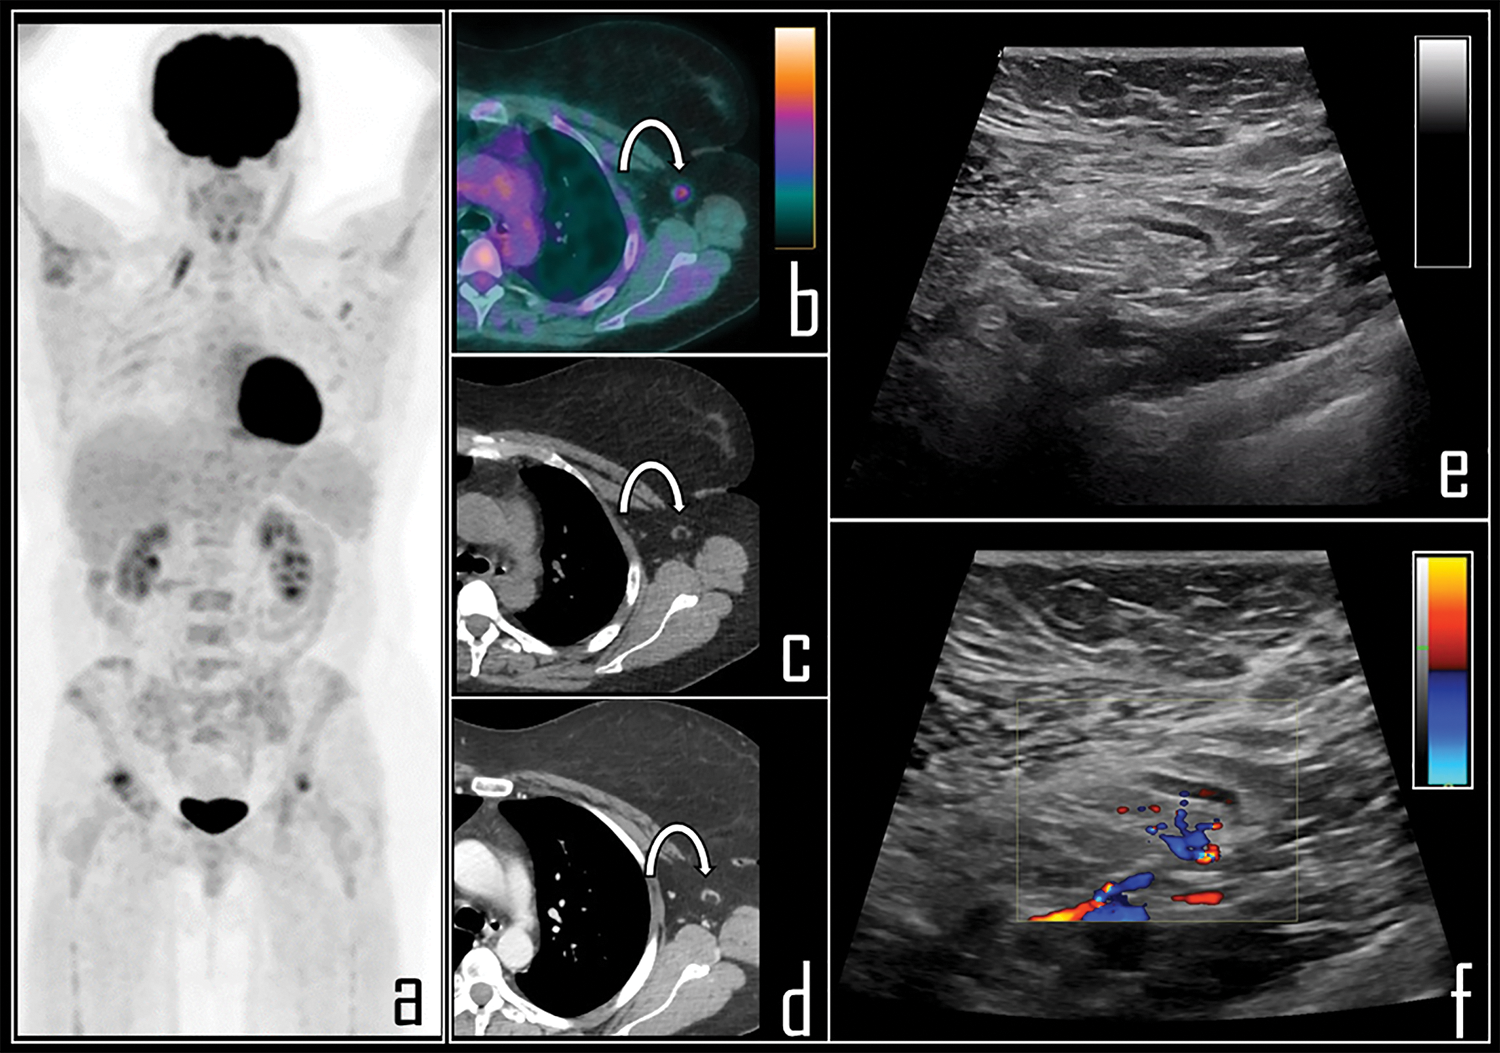

Figure 3: A 65-year-old female patient was examined by means of 2-[18F]FDG PET/CT during follow-up of ovarian cancer. PET Maximum Intensity Projection (a) was negative for disease relapse but showed a focal area of tracer uptake in the left axilla. Patient was previously submitted (14 days before) to second dose of COVID-19 vaccine in the deltoid muscle of left arm. Axial PET/CT view (b, curved arrow) shows the uptake in association with a 0.8 cm wide lymph node, with fatty hilum at correlative low dose axial CT (c, curved arrow). Subsequently, patient underwent whole body contrast enhanced CT, not showing disease relapse but confirming the axillary lymph node in left axilla, with low contrast enhancement (d, curved arrow). Ultrasonography was performed, displaying benign, 0.8 cm wide lymph node with regular shape (e), dominant central hilar flow and peripheral flow at color-doppler (f).

Particularly, low dose CT of PET/CT was significantly important, allowing to correctly depict benign features of 2-[18F]FDG-avid lymph nodes. These reactive lymph nodes generally presented low size, regular margins, ovoid shape and fatty hilum [15,16]. In selected cases, the radiologist also performed extemporaneous ultrasonography of the axillary region immediately following PET/CT scan, aimed to ensure diagnosis.

Ultrasonography confirmed the presence of oval, hypoechoic and homogeneous lymph nodes, with evident fatty hilum, showing central vascularity at Color Doppler. All these features were suggestive of benign, reactive lymph nodes.